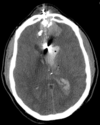

A patient initially presents after closed head injury with a GCS of 14. Head CT demonstrates a small amount of pneumocephalus. Two hours later, the patient becomes unresponsive (GCS 4). A repeat head CT is obtained (Fig. 1). What is the most appropriate next step in management?

Lumbar puncture to rule out meningitis.

Treatment with high flow oxygen.

Surgical evacuation of pneumocephalus.

Repeat head CT with fine cuts to identify a basal skull fracture.

Administer 1g/kg of mannitol.

A

Gas absorption can be facilitated by high flow oxygen but is not appropriate in the setting of acute neurological deterioration. Mannitol and lumbar puncture could exacerbate the scenario.